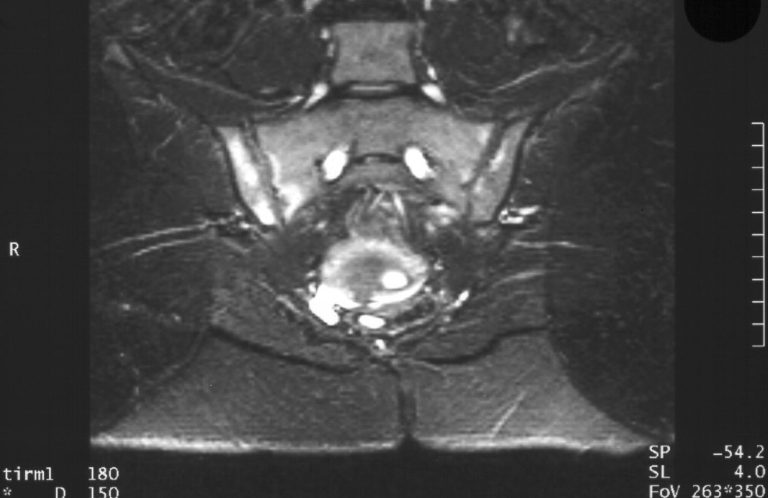

Die Kinderrheumatologie ist ein Subdisziplin der Kinder- und Jugendmedizin zur Behandlung und Erforschung von Entzündunsgerkrankungen, die den Bewegunsgapparat und/oder Haut, innere Organ oder Sinnesorgane betreffen.

Erkrankungen

Rheumatologische Erkrankungen betreffen den Bewegungsapparat, die Haut, innere Organe und Sinnesorgane. Beispiele?